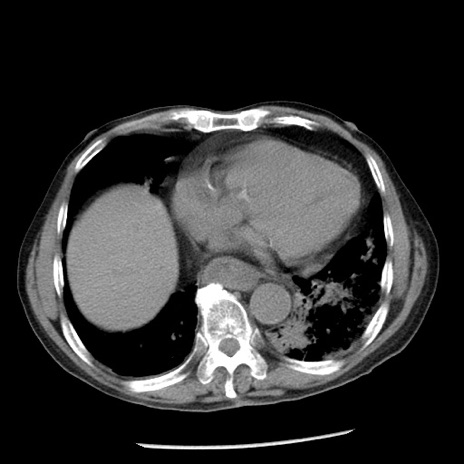

症例26(横断像)

【症例】80歳代男性

【主訴】嘔吐

【現病歴】昨晩2回嘔吐あり、今朝になっても嘔吐あり。来院。

【既往歴】胃潰瘍

【身体所見】意識清明、BT 37.6℃、BP 166/95mmHg、HR 100bpm、SpO2 97%、腹部:平坦・軟、腸蠕動音聴取良好、圧痛なし。

【データ】WBC 21900、CRP 1.46